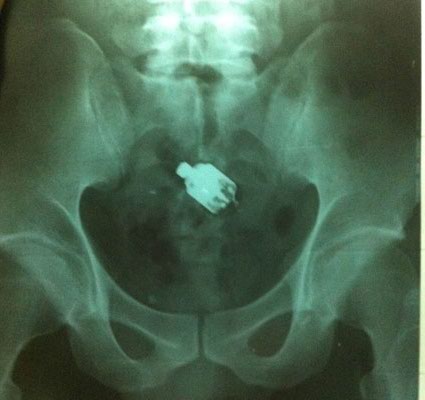

Sau khi rụt rè trình bày lại với bác sĩ về sự cố khi đang “hành sự” với máy rung (loại đồ chơi tình dục dành cho phụ nữ), bệnh nhân này được đưa đi chụp X-quang và nội soi. Hình ảnh siêu âm cho thấy dị vật nằm sâu trong trực tràng, cách cửa hậu môn đến khoảng 30cm. Các bác sĩ quyết định can thiệp để lấy dị vật ra.

Hình ảnh dị vật nằm sâu trong trực tràng trên phim chụp X-quang. Ảnh: H.Hải

Đầu tiên, bác sĩ chỉ định dùng dụng cụ lấy dị vật ra nhưng dị vật quá sâu, bệnh nhân đau đớn không thể can thiệp. Cuối cùng các bác sĩ đã phải tiến hành gây tê tủy sống kết hợp với nội soi để gắp dị vật.

“Lúc đầu dị vật ở ngay ống hậu môn, sau vào đến tận vùng đại tràng sigma với khoảng cách từ ống hậu môn vào điểm đó là 30cm”, BS Thụy Anh nói.